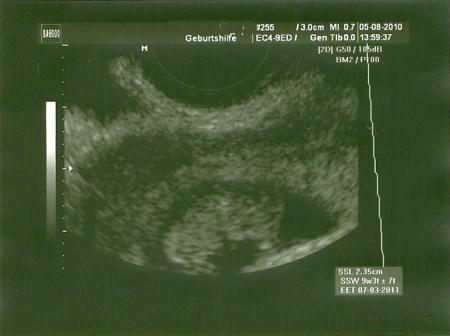

heute war endlich mein 1ter fa termin. ich war sooo nervös. es ist alles okay und gut entwickelt. der fa hat mich sogar eine woche vor gestuft, bin jetzt in der 9+3ssw. et wäre der 7.3.11. hab ein schöne bild bekommen bzw 2. und nächste woche donnerstag muss ich nochmal hin. dann gibs den mutterpass und nochmal us*freu* haben es dann den kids heute auch erzählt, mein mann wollte nicht mehr warten :-) der große war total am grinsen und die kleine am grübeln*hihi* glaub sie freuen sich beide jetzt drauf. reden nur noch vom baby u überlegen sich namen ;-) wenn ihr wollt, zeig ich später mal das bild, muss ich noch scannen oder so. lieben gruß steffie

bild hänge ich mal an, finds total süß

Ohja, das sieht auch schon richtig nach Baby aus....

ja find ich auch. im original ist das noch viel besser